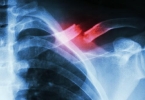

• 骨折术后多久能喝酒

骨折术后多久能喝酒

骨折术后一般需要1-3个月后才能饮酒,具体时间需根据骨折愈合情况、手术方式及个体差异综合评估。骨折术后早期组织修复阶段通常持续1-2个月,此时骨痂形成尚未稳定,酒精可能抑制成骨细胞活性,延缓愈合进程。酒精代 ...